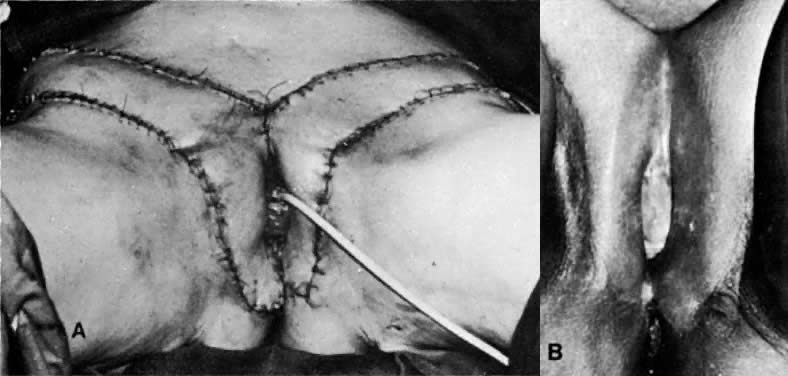

The presence of multifocal vulvar, perineal, and perianal lesions occasionally necessitates the removal of multiple areas of skin. Reapproximation is difficult. The technique of removing just the vulvar skin (i.e., skinning vulvectomy) and preserving the subcutaneous tissue and vulva blood supply is preferred.1 A rich bed of tissue is available for skin-graft applications (Fig. 1). Although operative time and hospital stay are lengthened when skinning vulvectomy and grafting are performed, better cosmetic results with few residual sequelae are obtained. Among these sequelae are graft-take failure in the range of 5% to 15% and an impairment of sensation in both the grafted area and the graft site. The mons pubis is a potential graft selection site.

Fig. 1. A. The vulva after “skinning vulvectomy” for multifocal lesions. B. A skin graft has been applied to the vulva.(Walton LA: Carcinoma in situ of the vulva. A Self Instructional Program. Chapel Hill, Health Sciences Consortium, 1982.)